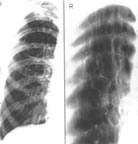

⑤X線胸片早期是間質性肺水腫,繼之是肺血樣改變,肺淤血主要表現為上肺的血管怒張和血管邊緣模糊。

④40%患者的X線胸片無心血管異常表現。

(3)X線胸片可能無典型結核表現,CT檢查有一定意義。

(5)X線胸片見兩肺瀰漫性顆粒或結節狀陰影,陰影可呈遊走性,肺尖部清晰。